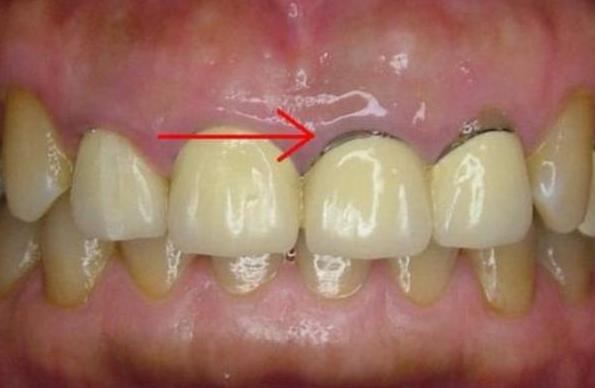

因为烤瓷牙制备不合格,烤瓷牙和真牙不够密合,包括贵金属烤瓷牙(黄金烤瓷牙)在内,无论采用那种金属都可能出现牙龈黑线。

烤瓷修复牙冠边缘与牙龈密合程度是判断烤瓷牙是否成功最重要的指标,密合不佳则会使细菌进行牙冠内,导致牙齿发言、牙龈萎缩、牙龈发黑等。

4、冠体材料更换